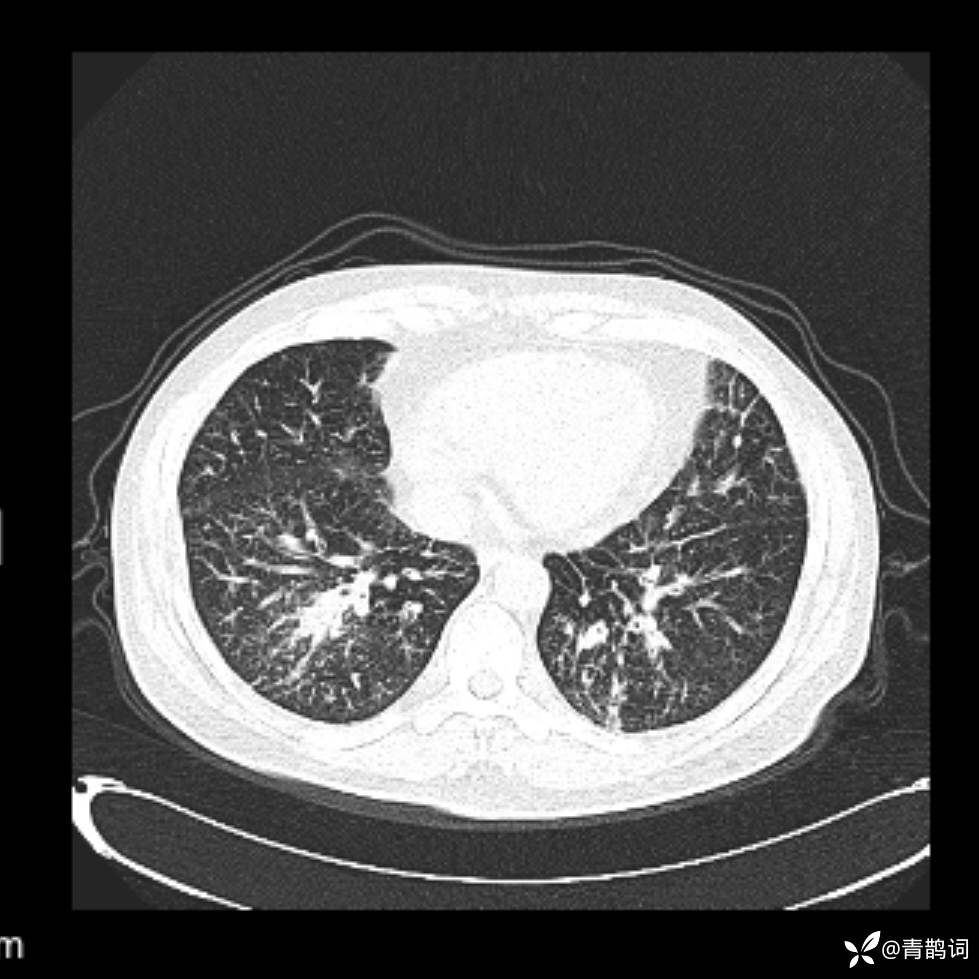

患者年龄:30岁。

患者性别:男。

简要病史:左颜面部肿胀2年,反复咳嗽咳痰,逐渐加重。

辅助检查